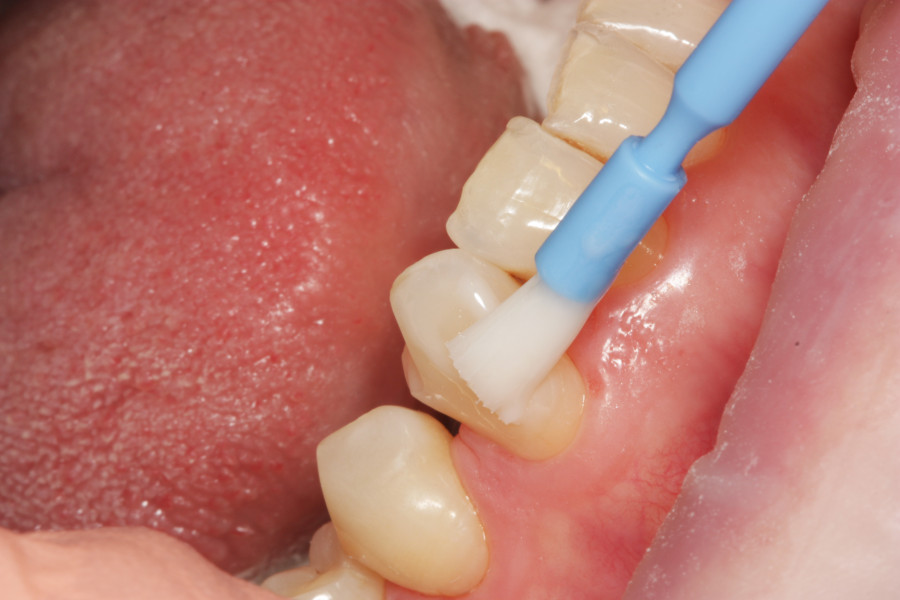

Po wypłukaniu jamy ustnej przez pacjentkę rozcieńczonym eludril classic przystąpiono do fluoryzacji preparatem clinpro varnish. Odizolowano wałeczkami ligniny zęby od śliny aby zapewnić ich suchość, a następnie pędzelkiem nałożono preparat na wszystkie zęby:

|

Celem fluoryzacji jest zmniejszenie nadwrażliwości zębów oraz wzmocnienie ich przez odbudowę mikroubytków szkliwa.